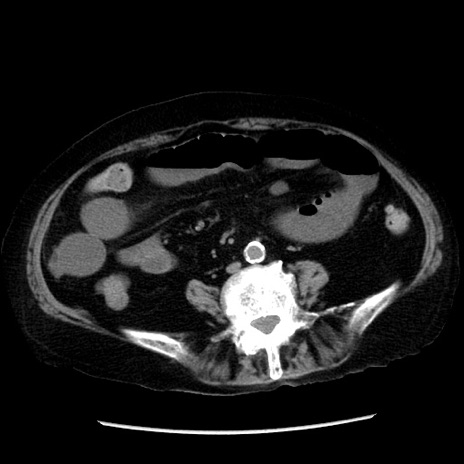

症例14(横断像)

【症例】 90歳代女性

【主訴】 腹痛・嘔吐

【現病歴】今朝から左側腹部痛を認めた。 経過観察していたが、嘔吐を認めたため来院。

【既往歴】 子宮癌術後

【身体所見】 意識清明、BP 127/54mmHg、P 98bpm Sp02 95%(RA)、BT 35.8°C、腹部平坦・軟腸ぜん動音聴取良好、右下腹部圧痛(+) 反跳痛なし

【データ】WBC 9800、CRP 0.46